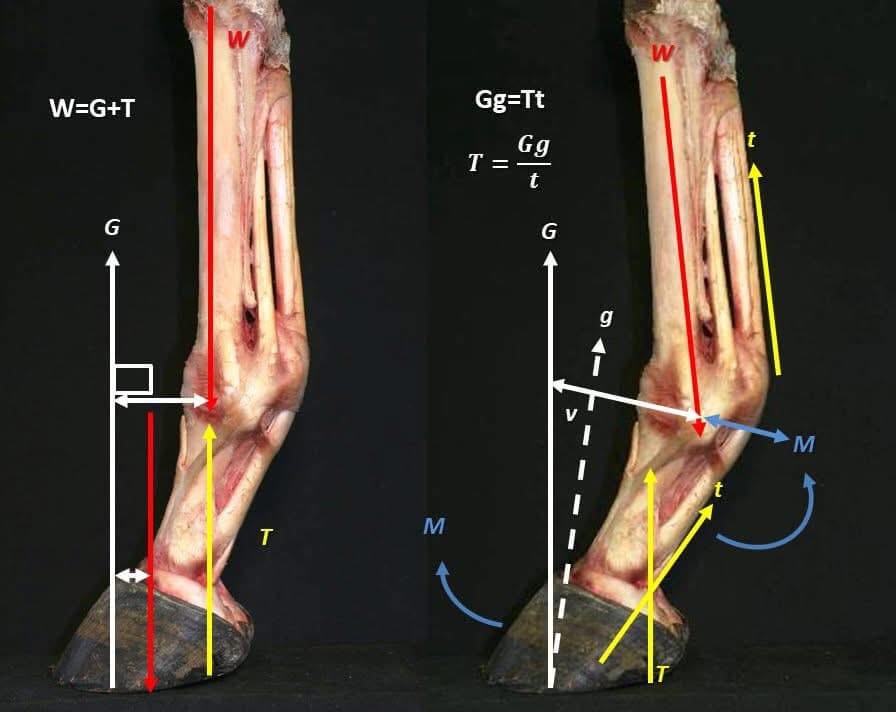

Toe Length and Lever Arm Mechanics

A longer toe increases the digital flexor moment arm, prolonging breakover and increasing the duration of peak fetlock extension (Clayton and Hobbs, 2017). Therapeutic trimming should therefore prioritise physiological toe shortening to reduce lever arm effects without excessive dorsal wall thinning.

The extensor moment acting on the limb is calculated by the ground reaction force acting through the COP times the distance of the COP from the centres of rotation. The extensor moment is a rotational and collapsing force acting on the limb.

Breakover Mechanics and Shoe Type Selection – The Digital Flexor Moment Arm

Toe length increases the moment arm acting around the distal interphalangeal joint. This delays heel lift and prolongs fetlock hyperextension, increasing suspensory strain duration (Clayton and Hobbs, 2017).